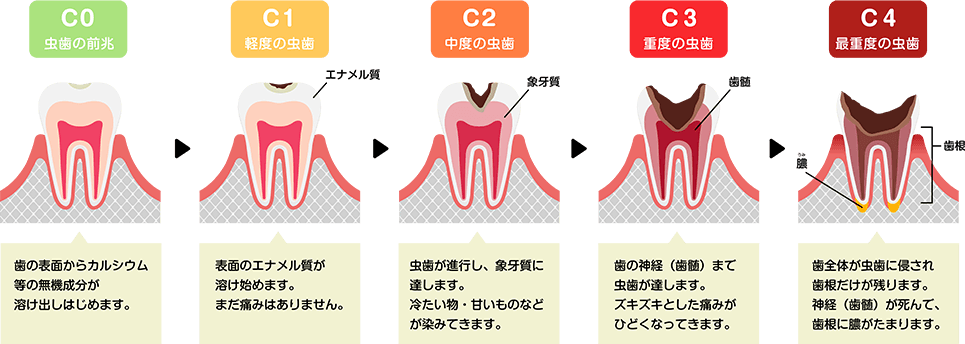

また、大切な歯を1本でも多く残すため、むし歯を検出する装置やレントゲンを用いることで精確に診断し、できるだけ「削らない」「抜かない」治療を行います。

当院ではレーザー光を照射することで、むし歯の進行状態を数値化して精確に測定することができる、ダイアグノデントを導入しております。 ダイアグノデントを使用することにより初期のむし歯も早期発見ができ、早期治療に繋がります。